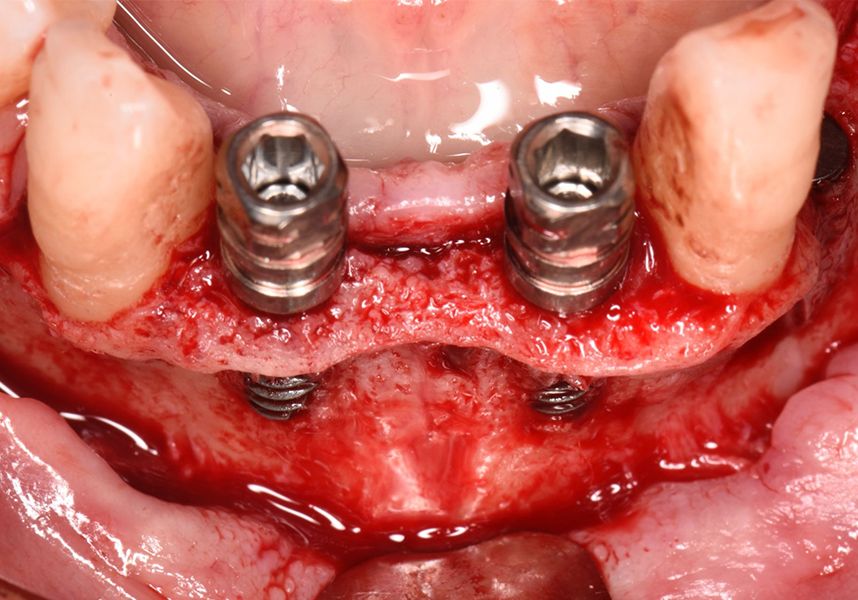

Respecting the three-dimensionally correct position of the implant led to bone fenestration, leaving the apical part of the apex of the implant exposed almost to the mid-point of its length at 42 and a third in 32.

To treat the defect, bone regeneration was carried out simultaneous to the surgical process, with an autologous bone graft from the patient. In the internal part of the graft we used autologous cortical bone obtained by scraping (Safescraper) and from the biological drilling, at low revolutions and without irrigation, from the other implant beds. In the external layer of the regeneration we used a xenograft (Genoss, Osteogenos) and this was covered with a reabsorbable collagen barrier membrane (Evolution STD, Osteogenos).

The membrane was sutured with PGA reabsorbable suture to the periosteum to secure it, thus avoiding subsequent reentry to remove fixings such as tacks.